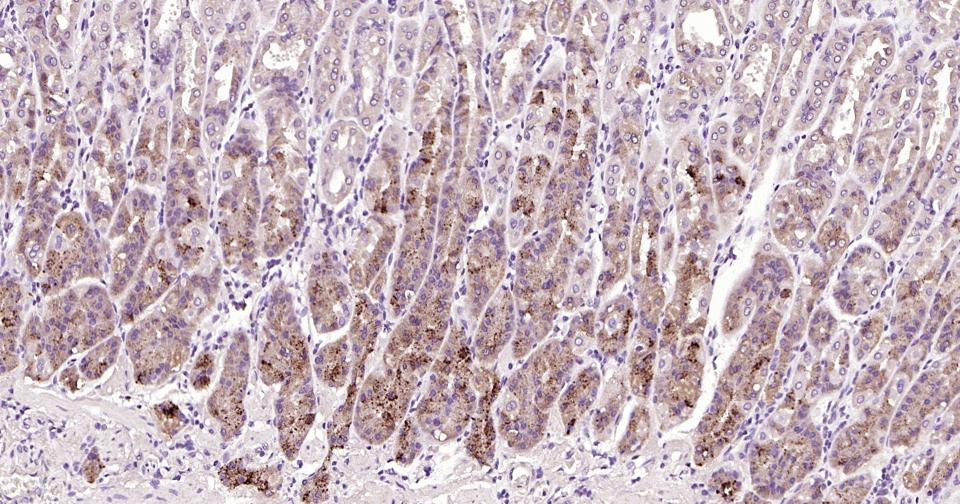

| 应用 | 已检合格种属 | 预测种属 | 推荐稀释比例 |

|---|---|---|---|

| IHC-P | Human, Mouse, Rat | 1:100-500 | |

| IHC-F | Human, Mouse, Rat | 1:100-500 | |

| IF | Human, Mouse, Rat | 1:100-500 |

交叉反应: Human, Mouse, Rat